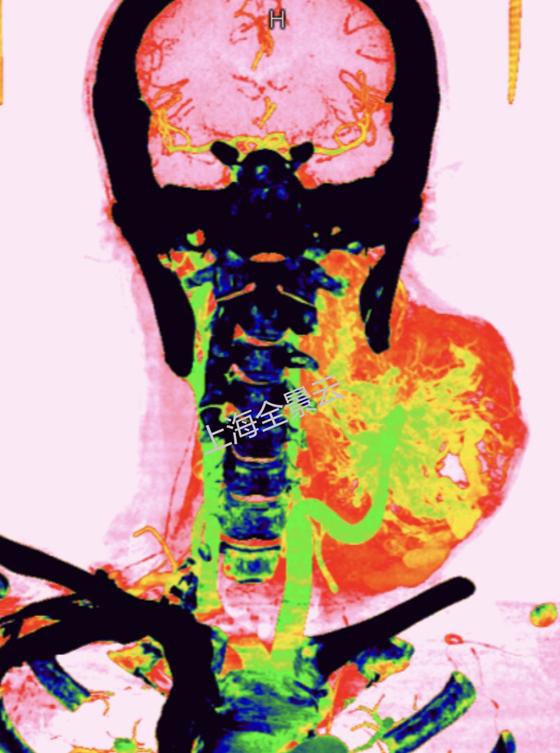

随后全景医生将动静脉图像叠加融合后,在西门子Syngo.via医学影像后处理系统(VB20版)处理得到颈部动静脉的CT三维图像,并使用电影级的三维可视化实影渲染技术(cVRT),逼真显示出肿块内动脉与静脉的走行关系与三维结构。

再进行剖面重建并将动脉静脉标识为不同颜色,直观显示出这个肿块内穿行着颈总动脉,并发出“蔓藤样”迂曲的动脉血管网,表面覆盖着静脉血管团,然后汇入上腔静脉(见下图),诊断呼之欲出,这是一个罕见的左侧颈部巨大血管瘤。